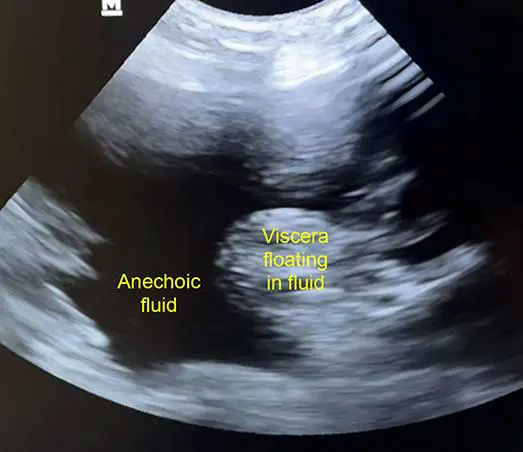

A point-of-care ultrasound, if available, should be readily performed. Free fluid shows as hypoechoic or anechoic regions, with small volumes located most commonly cranial to the liver or caudal to the bladder.

Increasing serial measurements of abdominal fluid pockets by ultrasound gives rapid tangible evidence of ongoing haemorrhage and is more reliable and reproducibly assessed across clinicians than patient mental acuity, PCV changes or hypovolaemic shock clinical parameters.